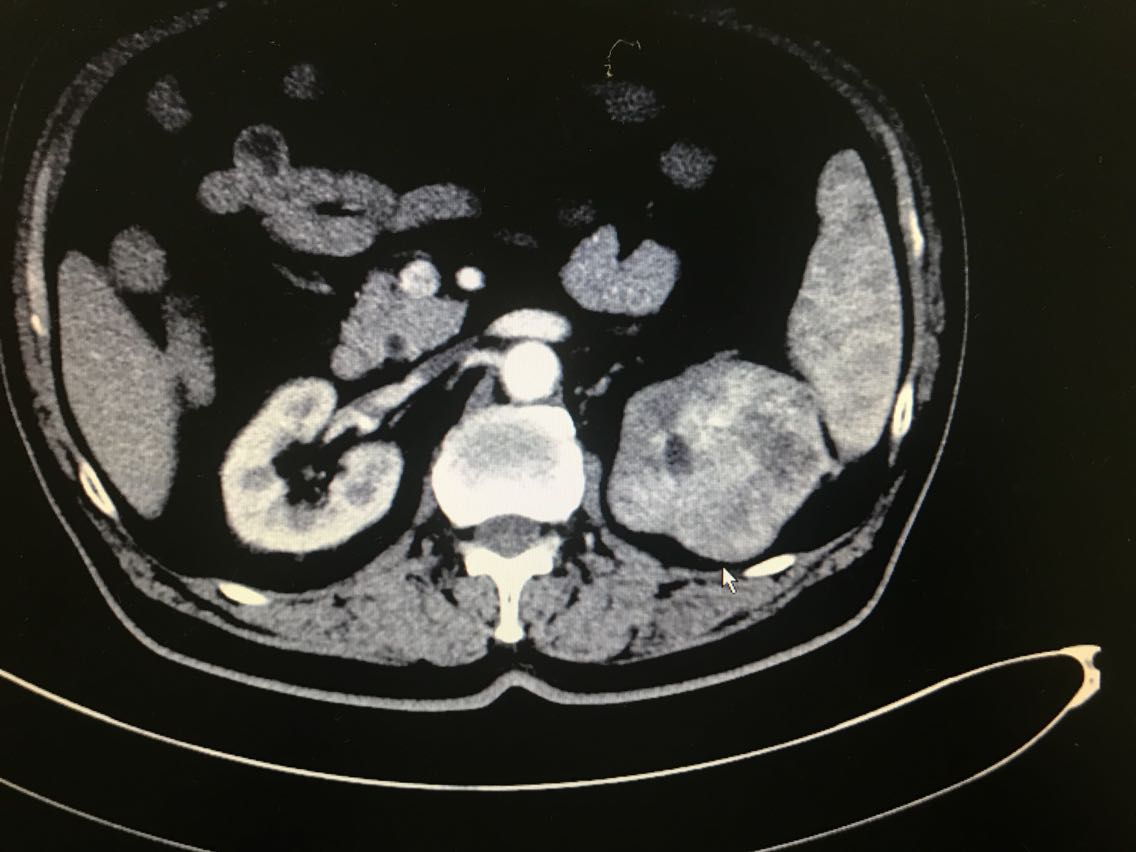

患者男性,81岁。 主诉:血尿伴左侧腰痛一月余 现病史:患者一月前出现血尿,伴左侧腰痛,于当地医院就诊,诊断为左侧肾盂占位。患者为求进一步治疗来我院门诊,门诊以肾盂恶性肿瘤收入院。起病以来,患者睡眠饮食尚可,二便无明显改变,体重未减。 既往史无特殊。

查体无特殊。 辅助检查: 全腹CT示:左肾上极肿块,侵犯左肾上盏并突入左肾盂,性质:左肾细胞癌可能性大,肾盂癌待排,结合临床。

诊断:左肾占位:肾盂癌? 治疗:腹腔镜左肾盂癌根治术

患者左肾占位,肾盂癌、肾癌均有可能,然而两种疾病的手术方式并不一样。前者需要切除同侧输尿管以及部分膀胱,而后者却不需要。那么在诊断不明确的情况下,手术方式以前者为宜。